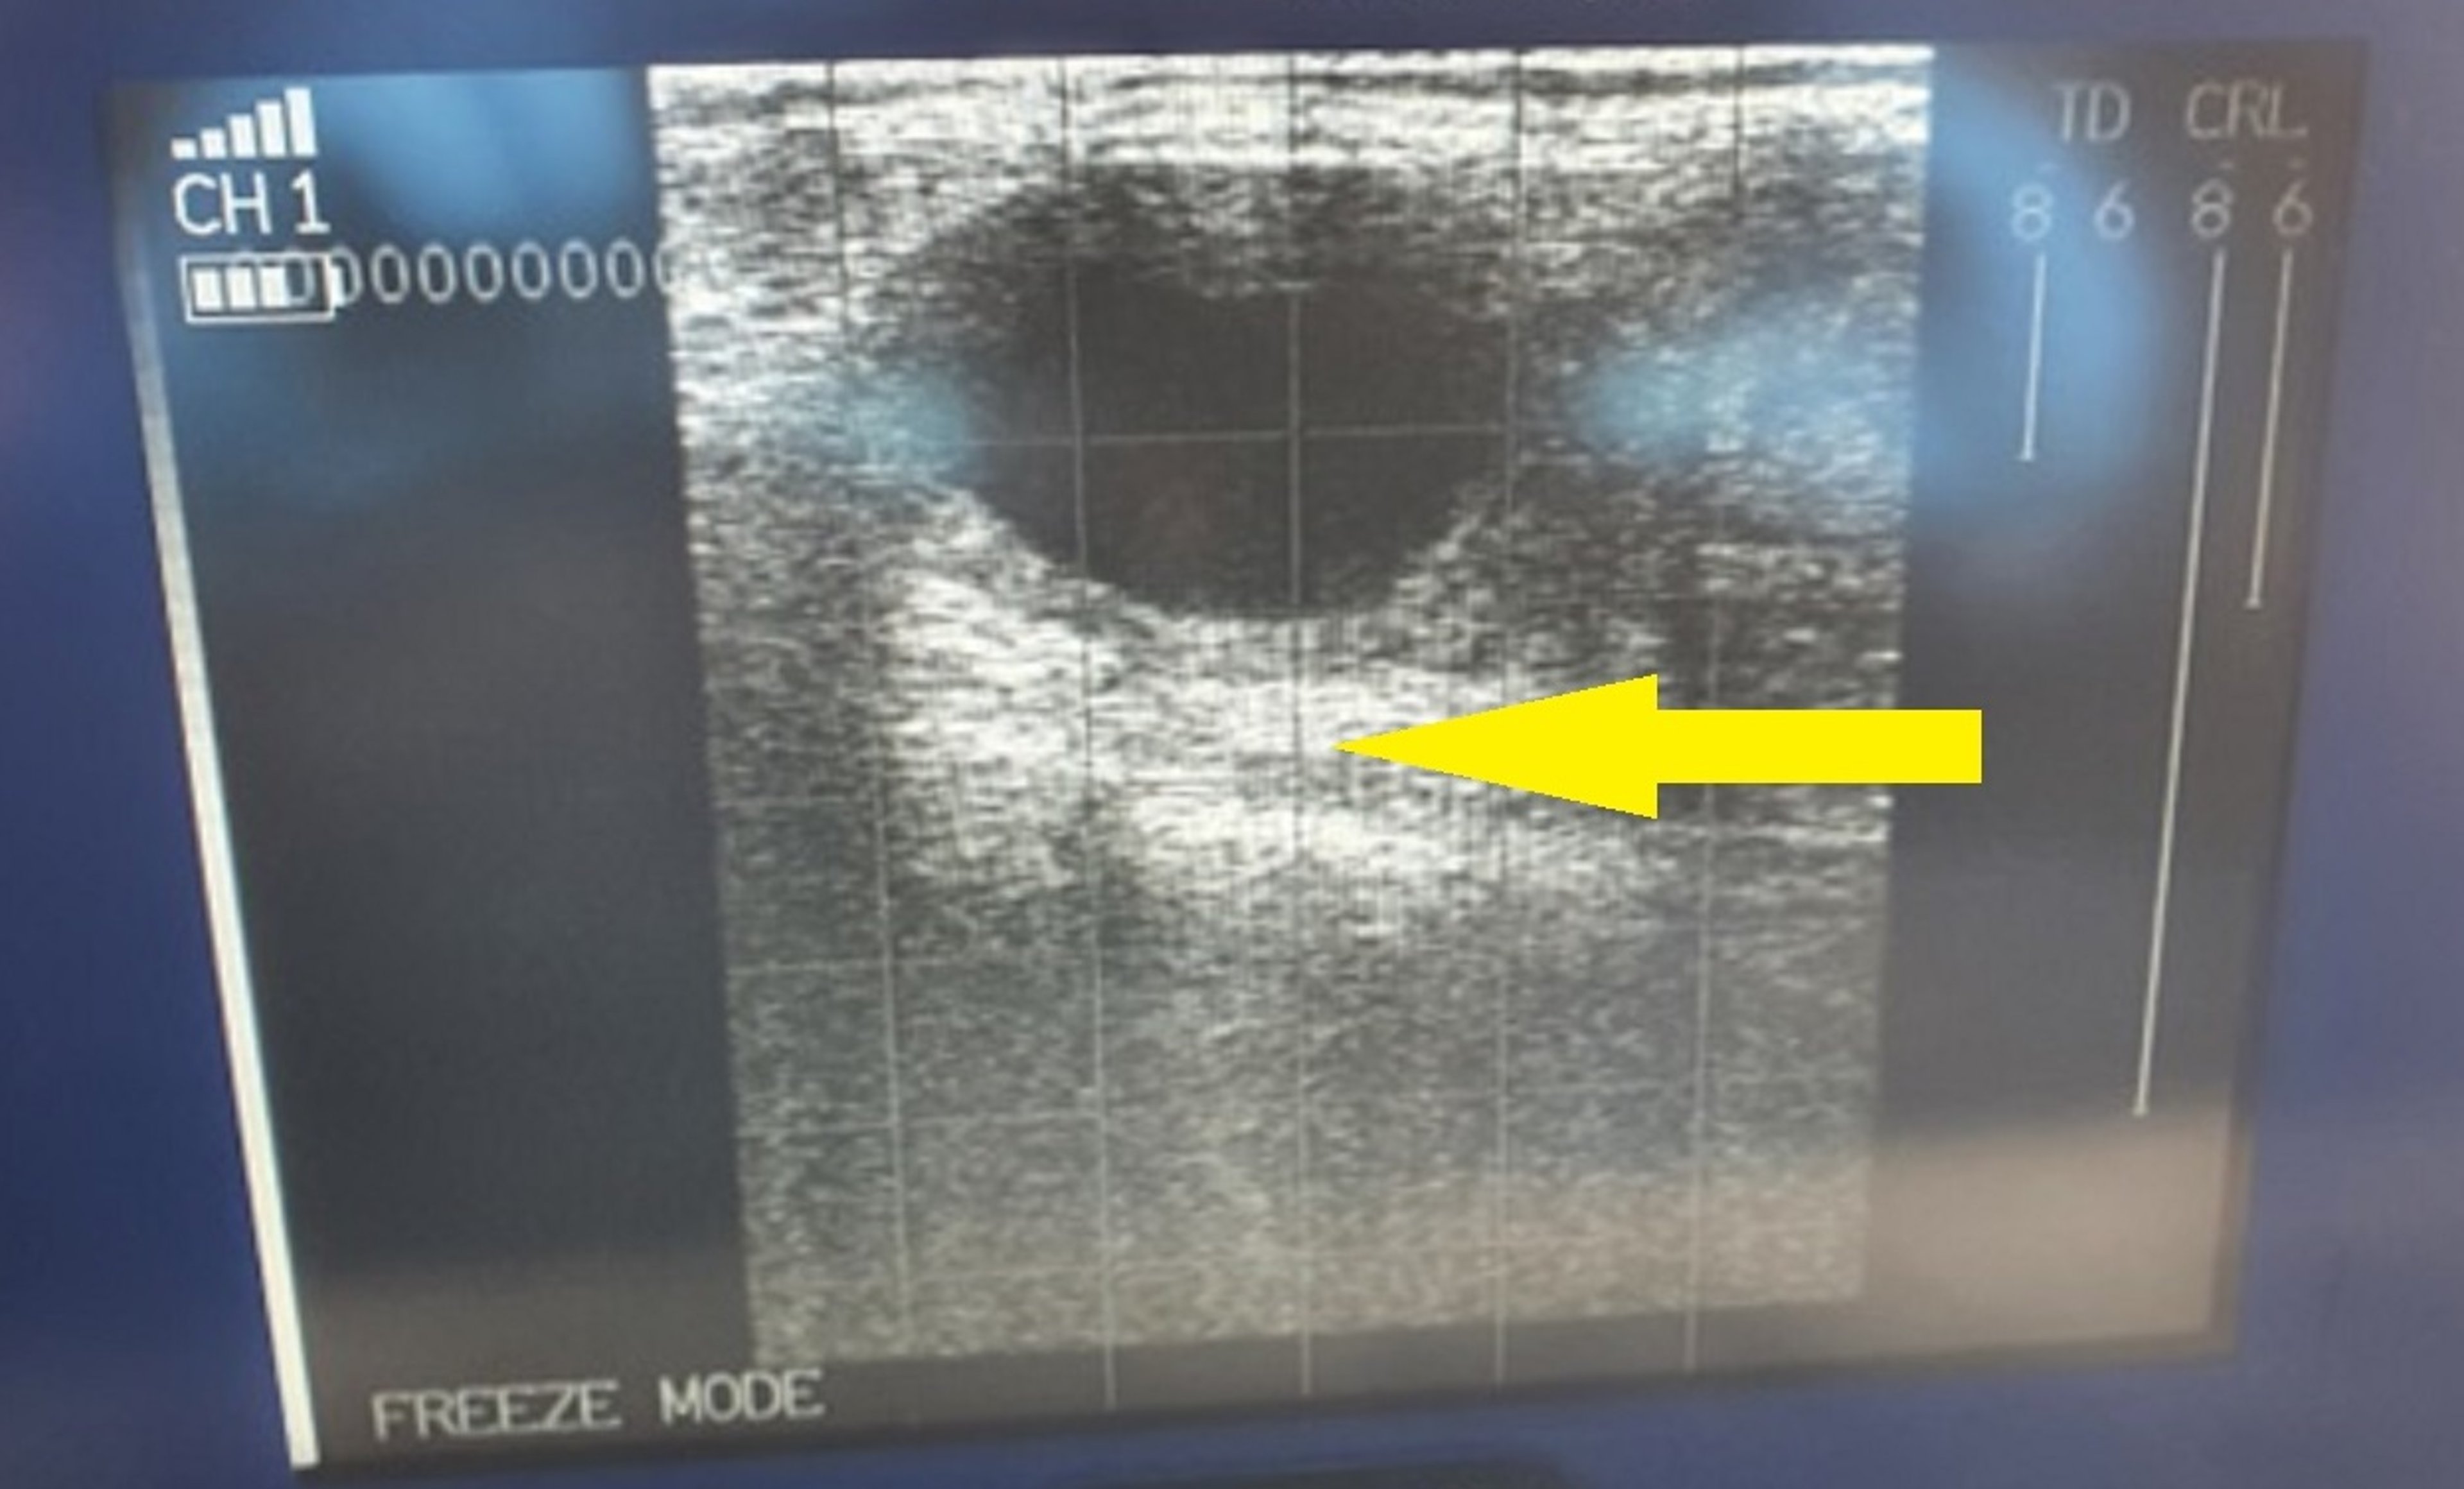

Ultrasonographic image showing a luteal cyst > 30 mm in diameter, with a wall > 3 mm thick (arrow), in the ovary of a cow.

Luteal cystic ovary disease is characterized by enlarged ovaries with one or more cysts that have walls thicker than follicular cyst walls because of a lining of luteal tissue. Incidence ratios of follicular versus luteal cysts vary greatly because of differences in the diagnostic skills of individual veterinarians. Typically, luteal cystic ovary disease is defined as the presence of a fluid-filled ovarian structure > 25 mm in diameter, with a wall diameter > 3 mm, persisting > 10 days in the absence of a corpus luteum and usually associated with abnormal reproductive signs. Normal formation of lacunae in the corpus luteum may be incorrectly classified as luteal cystic ovary disease.

Luteal cysts are differentiated from follicular cysts on the basis of palpable characteristics of both their structure and the uterus and, to some extent, on the basis of the cow’s behavior. Progesterone assay and ultrasonographic examination can assist such differentiation; with either method, however, a final diagnostic decision remains somewhat subjective.

Ultrasonographic examination is increasingly common in modern practice and facilitates the diagnosis of ovarian structures. Luteal cysts also respond to the treatment with hCG and Gn-RH that is effective against follicular cysts; however, the next estrus could be delayed as much as 21 days after treatment.